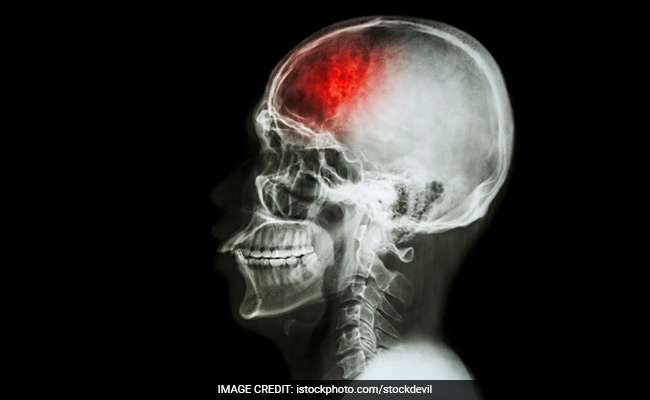

World Stroke Day 2017: The 5 Signs Of Stroke You Must Know To Save A Life

Strokes occur due to problems with the blood supply to the brain; either the blood supply is blocked or a blood vessel within the brain ruptures. Read on to know about early signs of stroke this World Stroke Day 2017.